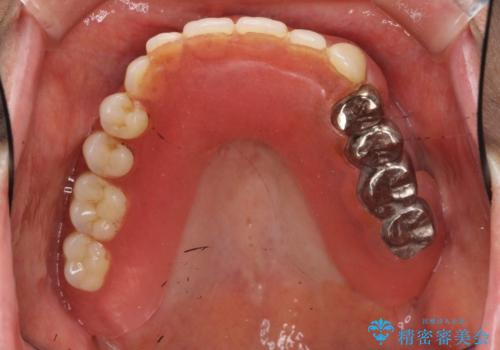

- 他院にて入れ歯を入れたが全体的に左に傾いており、咬みにくく、見た目も気になるといらっしゃった方の症例です。

診査の結果、虫歯が進行し保存できない歯が多かったため抜歯し、磁性アタッチメントを用いたインプラントオーバーデンチャーによる咬合及び見た目の改善を行いました。